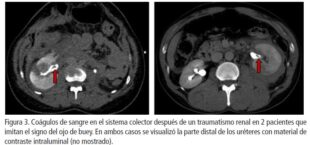

Sin embargo, la formación de tejido fibrótico a partir de la pérdida de orina puede hacer que el acceso al hilio renal y al uréter seccionado desafiante en la reparación diferida. Los diagnósticos diferenciales incluyen lesiones parciales ureterales o de pelvis renal y coágulos de sangre en el sistema colector. Los defectos de llenado de los coágulos sanguíneos intraluminales que pueden imitar la apariencia de un ojo de buey (fig.3), pero el contraste intraluminal generalmente se puede ver distal al defecto de llenado y se puede diferenciar de la ruptura de la JUP mediante una ureteropielografía retrógrada.